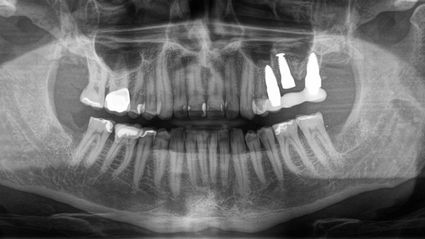

Da ich von dem Konzept zu 100% überzeugt bin, habe ich mich im Februar 2018 für eine Operation bei Dr. Ulrich Volz in der Swiss Biohealth Clinic entschieden. Unter örtlicher Betäubung entfernte Dr. Volz vier Bleichzähne und einen wurzelbehandelten Zahn (27). Er implantierte drei SDS-Keramikimplantate in den linken Oberkiefer, inklusive Sinuslift.